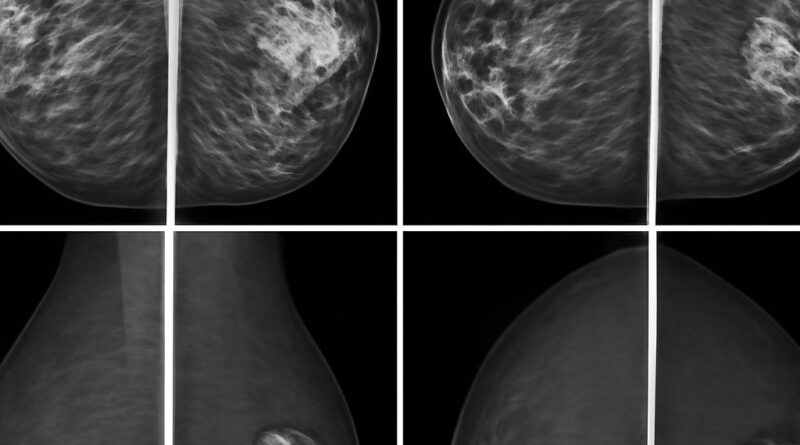

Not everyone with a breast concern needs MRI. Mammography remains the primary screening tool for the general population, with ultrasound as a supplement for dense breast tissue. Breast MRI is reserved for situations where the additional sensitivity and specificity of the modality changes clinical management, either by ruling out additional disease or guiding decisions about surgical approach. Your radiologist and ordering physician make this determination based on clinical context.

What Breast MRI Detects

An MRI of the breast uses contrast dye (gadolinium) to evaluate blood flow patterns in breast tissue. Cancer tends to enhance quickly due to its blood supply characteristics, which shows up distinctly on MRI sequences. The scan also evaluates lymph nodes in the axilla, chest wall involvement, and skin changes. For implant evaluation, specific sequences without contrast detect silicone outside the implant shell, which indicates rupture.